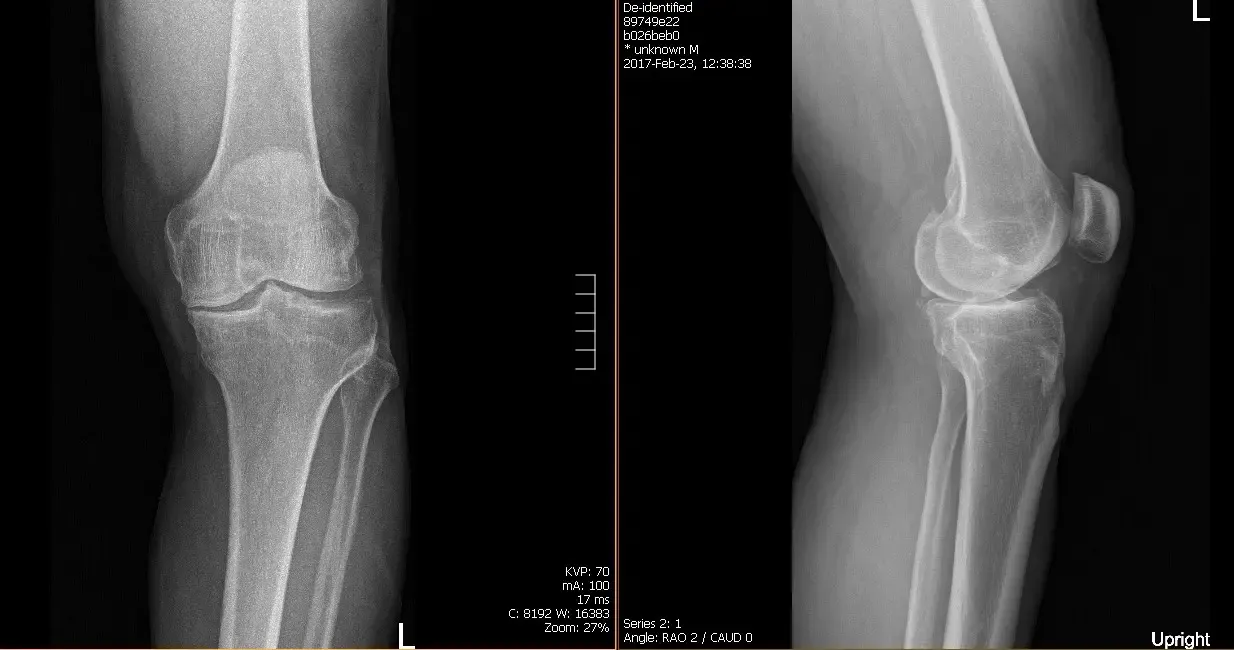

Su HEP consistió en ejercicios isométricos de cuádriceps, isquiotibiales y glúteos, un estiramiento de flexión de rodilla sentado y un colgamiento de rodilla supina. Se indicó al paciente que continuara con su HEP además del nuevo programa HEP que le administraría en fisioterapia ambulatoria. Las pruebas prequirúrgicas revelaron cambios degenerativos osteoartríticos moderados.

El paciente se sometió a una artroplastia de rodilla total izquierda utilizando un implante personalizado. Durante el procedimiento, su cirujano observó que ya había osteoartritis avanzada. Se utilizó un enfoque parapatelar medial, se colocó la guía de resección tibial tras la exposición de la tibia y se realizó y revisó la resección tibial.